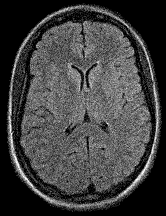

Refer to caption

(b) (17.62, 0.57, 0.19)

(c) (18.23, 0.58, 0.26)

Figure 6: Visualized FA images obtained from diffusion MRI with super-resolution reconstructions. The up-sampled image (c) is wrongly judged to have better quality than the high-resolution reconstruction (b) by PSNR and SSIM, LPIPS judges this task correctly.

FR-IQA mismatch

We can see in Figure 6 that PSNR and SSIM misjudge the visual quality of the high-resolution reconstruction in (b) in comparison to the up-sampled image in (c). Clearly, that image has worse visual quality than the one in (b). It is per default more blurry and does not provide sufficient anatomical details. LPIPS yields more sufficient results in this example, and correctly attributes (c) a higher quality error.

In this example it has to be noted that the computed IQA numbers are generally quite low, because the resulting FA images do not necessarily have to have the same range or distribution as the reference image. Therefore, in order to compare the reconstruction quality directly, this task generally benefits from NR-IQA evaluation.